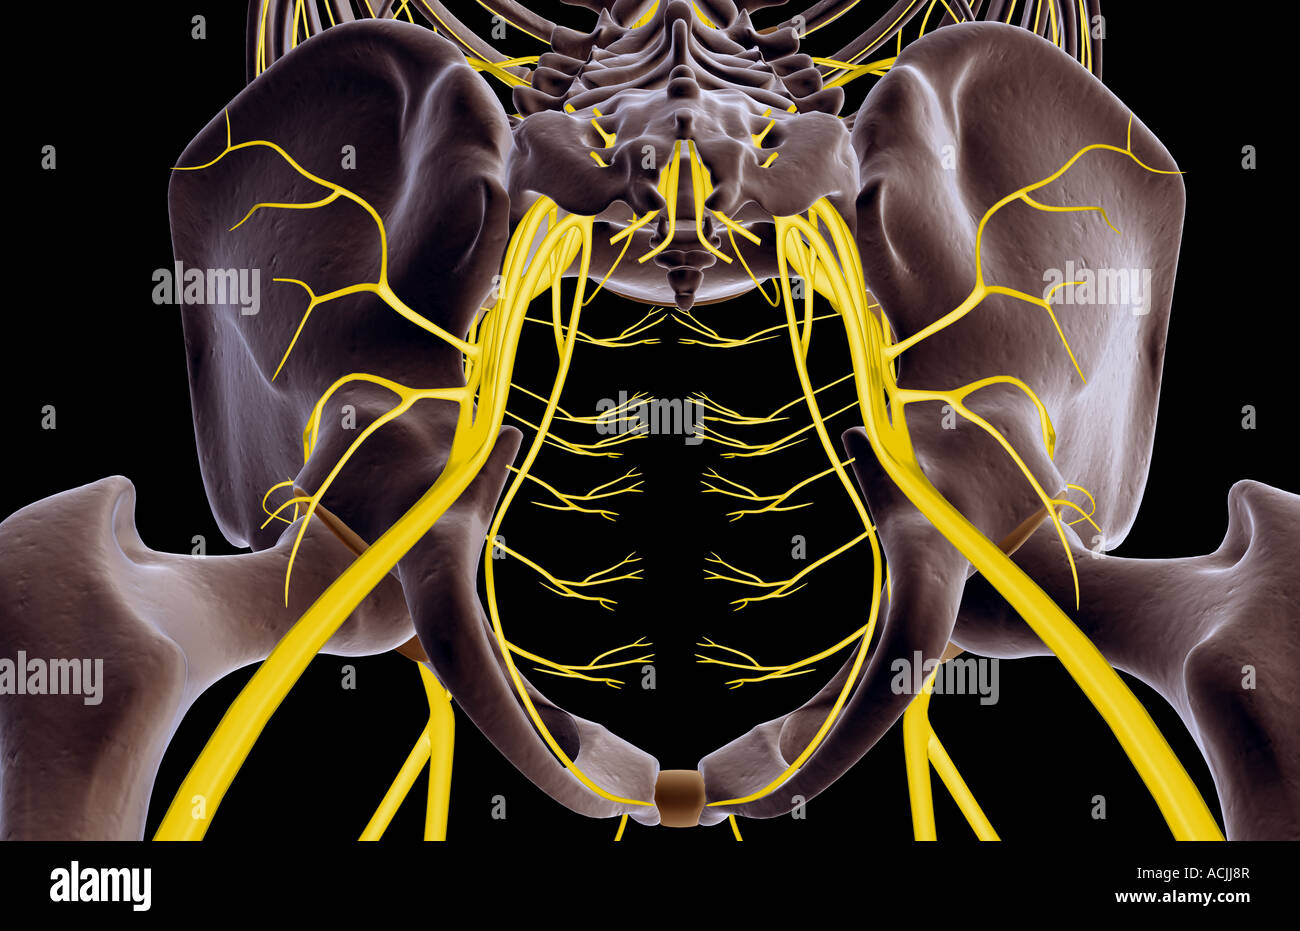

Les Nerfs du pelvis Banque D'Imageshttps://www.alamyimages.fr/image-license-details/?v=1https://www.alamyimages.fr/photo-image-les-nerfs-du-pelvis-13171078.html

Les Nerfs du pelvis Banque D'Imageshttps://www.alamyimages.fr/image-license-details/?v=1https://www.alamyimages.fr/photo-image-les-nerfs-du-pelvis-13171078.htmlRFACJJ8R–Les Nerfs du pelvis